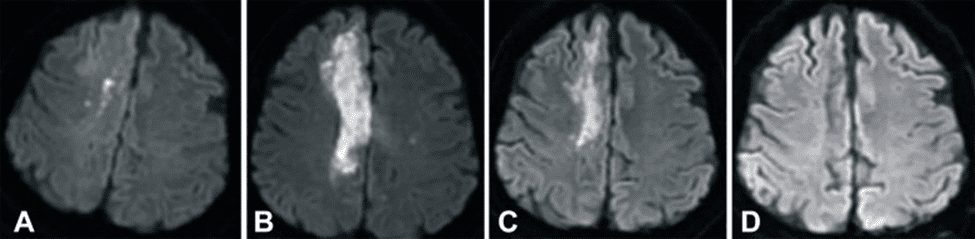

Níže uvedené snímky zobrazují magnetickou rezonanci (MRI) mozku pacienta s cévní mozkovou příhodou, která byla pořízena (A) 2 hodiny po mrtvici, (B) 1 den po transfuzi pupečníkové krve (UCB), (C) 3 měsíce po transfuzi UCB a (D) 6 měsíců po transfuzi UCB. Tyto snímky MRI byly pořízeny pomocí difuzně váženého zobrazení (DWI), což je technika, která zvýrazňuje otok mozku a dokáže přesně odhalit ischemickou cévní mozkovou příhodu během několika minut od jejího vzniku5. Na snímcích je jasně vidět, že edém (otok z přebytku tekutiny) v pravém mozkovém laloku pacienta zmizel během 6 měsíců po infuzi pupečníkové krve.

Skutečným testem toho, jak dobře terapie léčí mrtvici, je, když se pacientovi vrátí schopnosti, které byly narušeny. V tomto případě pacient trpěl ochrnutím levé strany těla (hemiplegií) v důsledku infarktu na pravé straně mozku. Po infuzi pupečníkové krve se pacientovi začala vracet pohyblivost a ve třetím měsíci už mohl chodit s omezenou pomocí. Pacient byl po léčbě pupečníkovou krví sledován po dobu jednoho roku. Během této doby se jeho skóre na škále NIHSS (NIH Stroke Scale) snížilo z 9 na 1, skóre na Berg Balance Scale se zvýšilo z 0 na 48 a Barthelův index, který hodnotí aktivity denního života, se během ročního sledování zvýšil z 0 na 90. V průběhu sledování se jeho skóre na škále NIHSS snížilo z 0 na 1. Na konci sledovaného období se pacientovi plně obnovily motorické funkce a mohl žít samostatně.